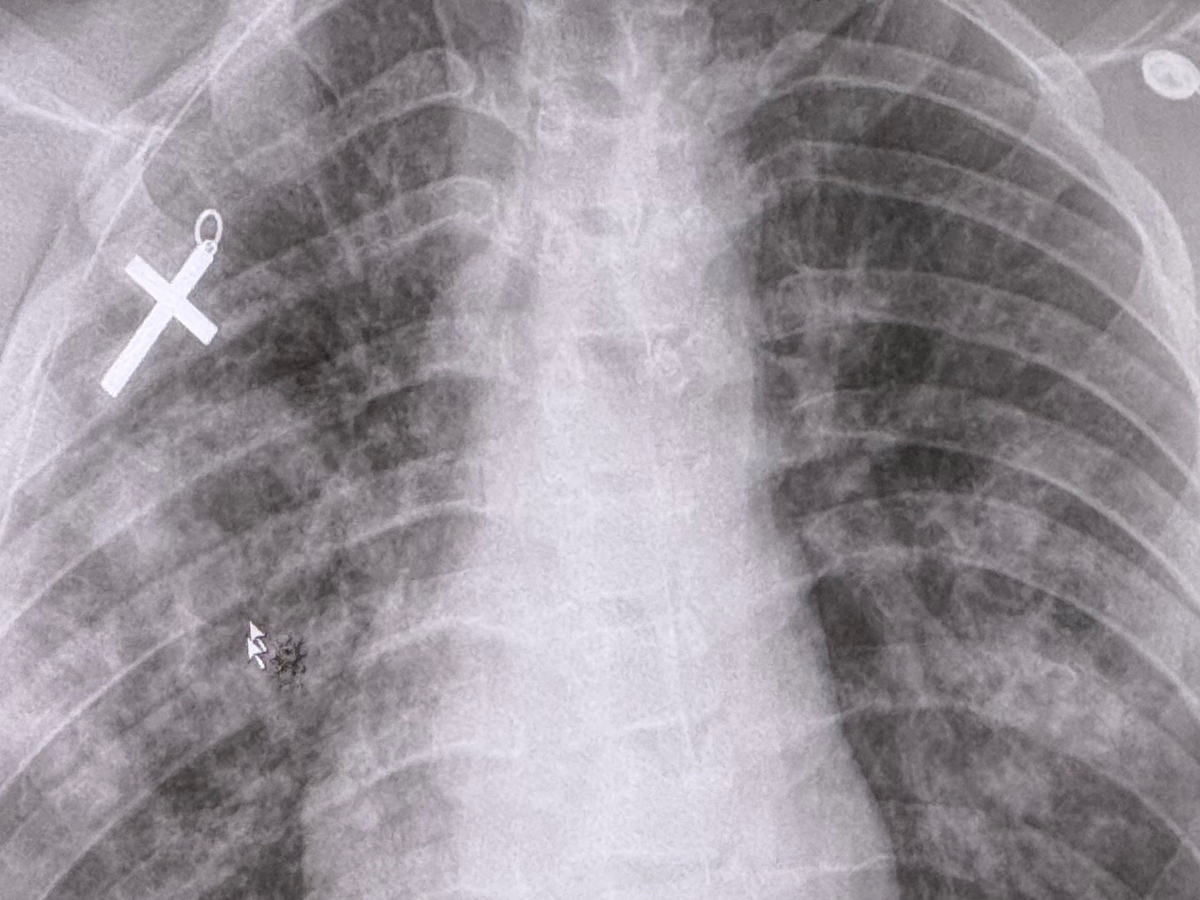

Preston has always been rooted in the Lord, and God has been prevalent through every step since the very beginning. A few years ago, he was gifted a cross necklace from his grandmother, which he never took off. Once in the trauma room in the ER, Preston’s mother, Chelsea, was given all his belongings. They couldn’t find his cross, only the chain. However, during his first CAT scan, within an hour of his arrival, they found that it was pressed into his back! We uploaded the scan so that you too can be blessed by it. GOD loves us all, and HE has not forsaken this young man, nor you.